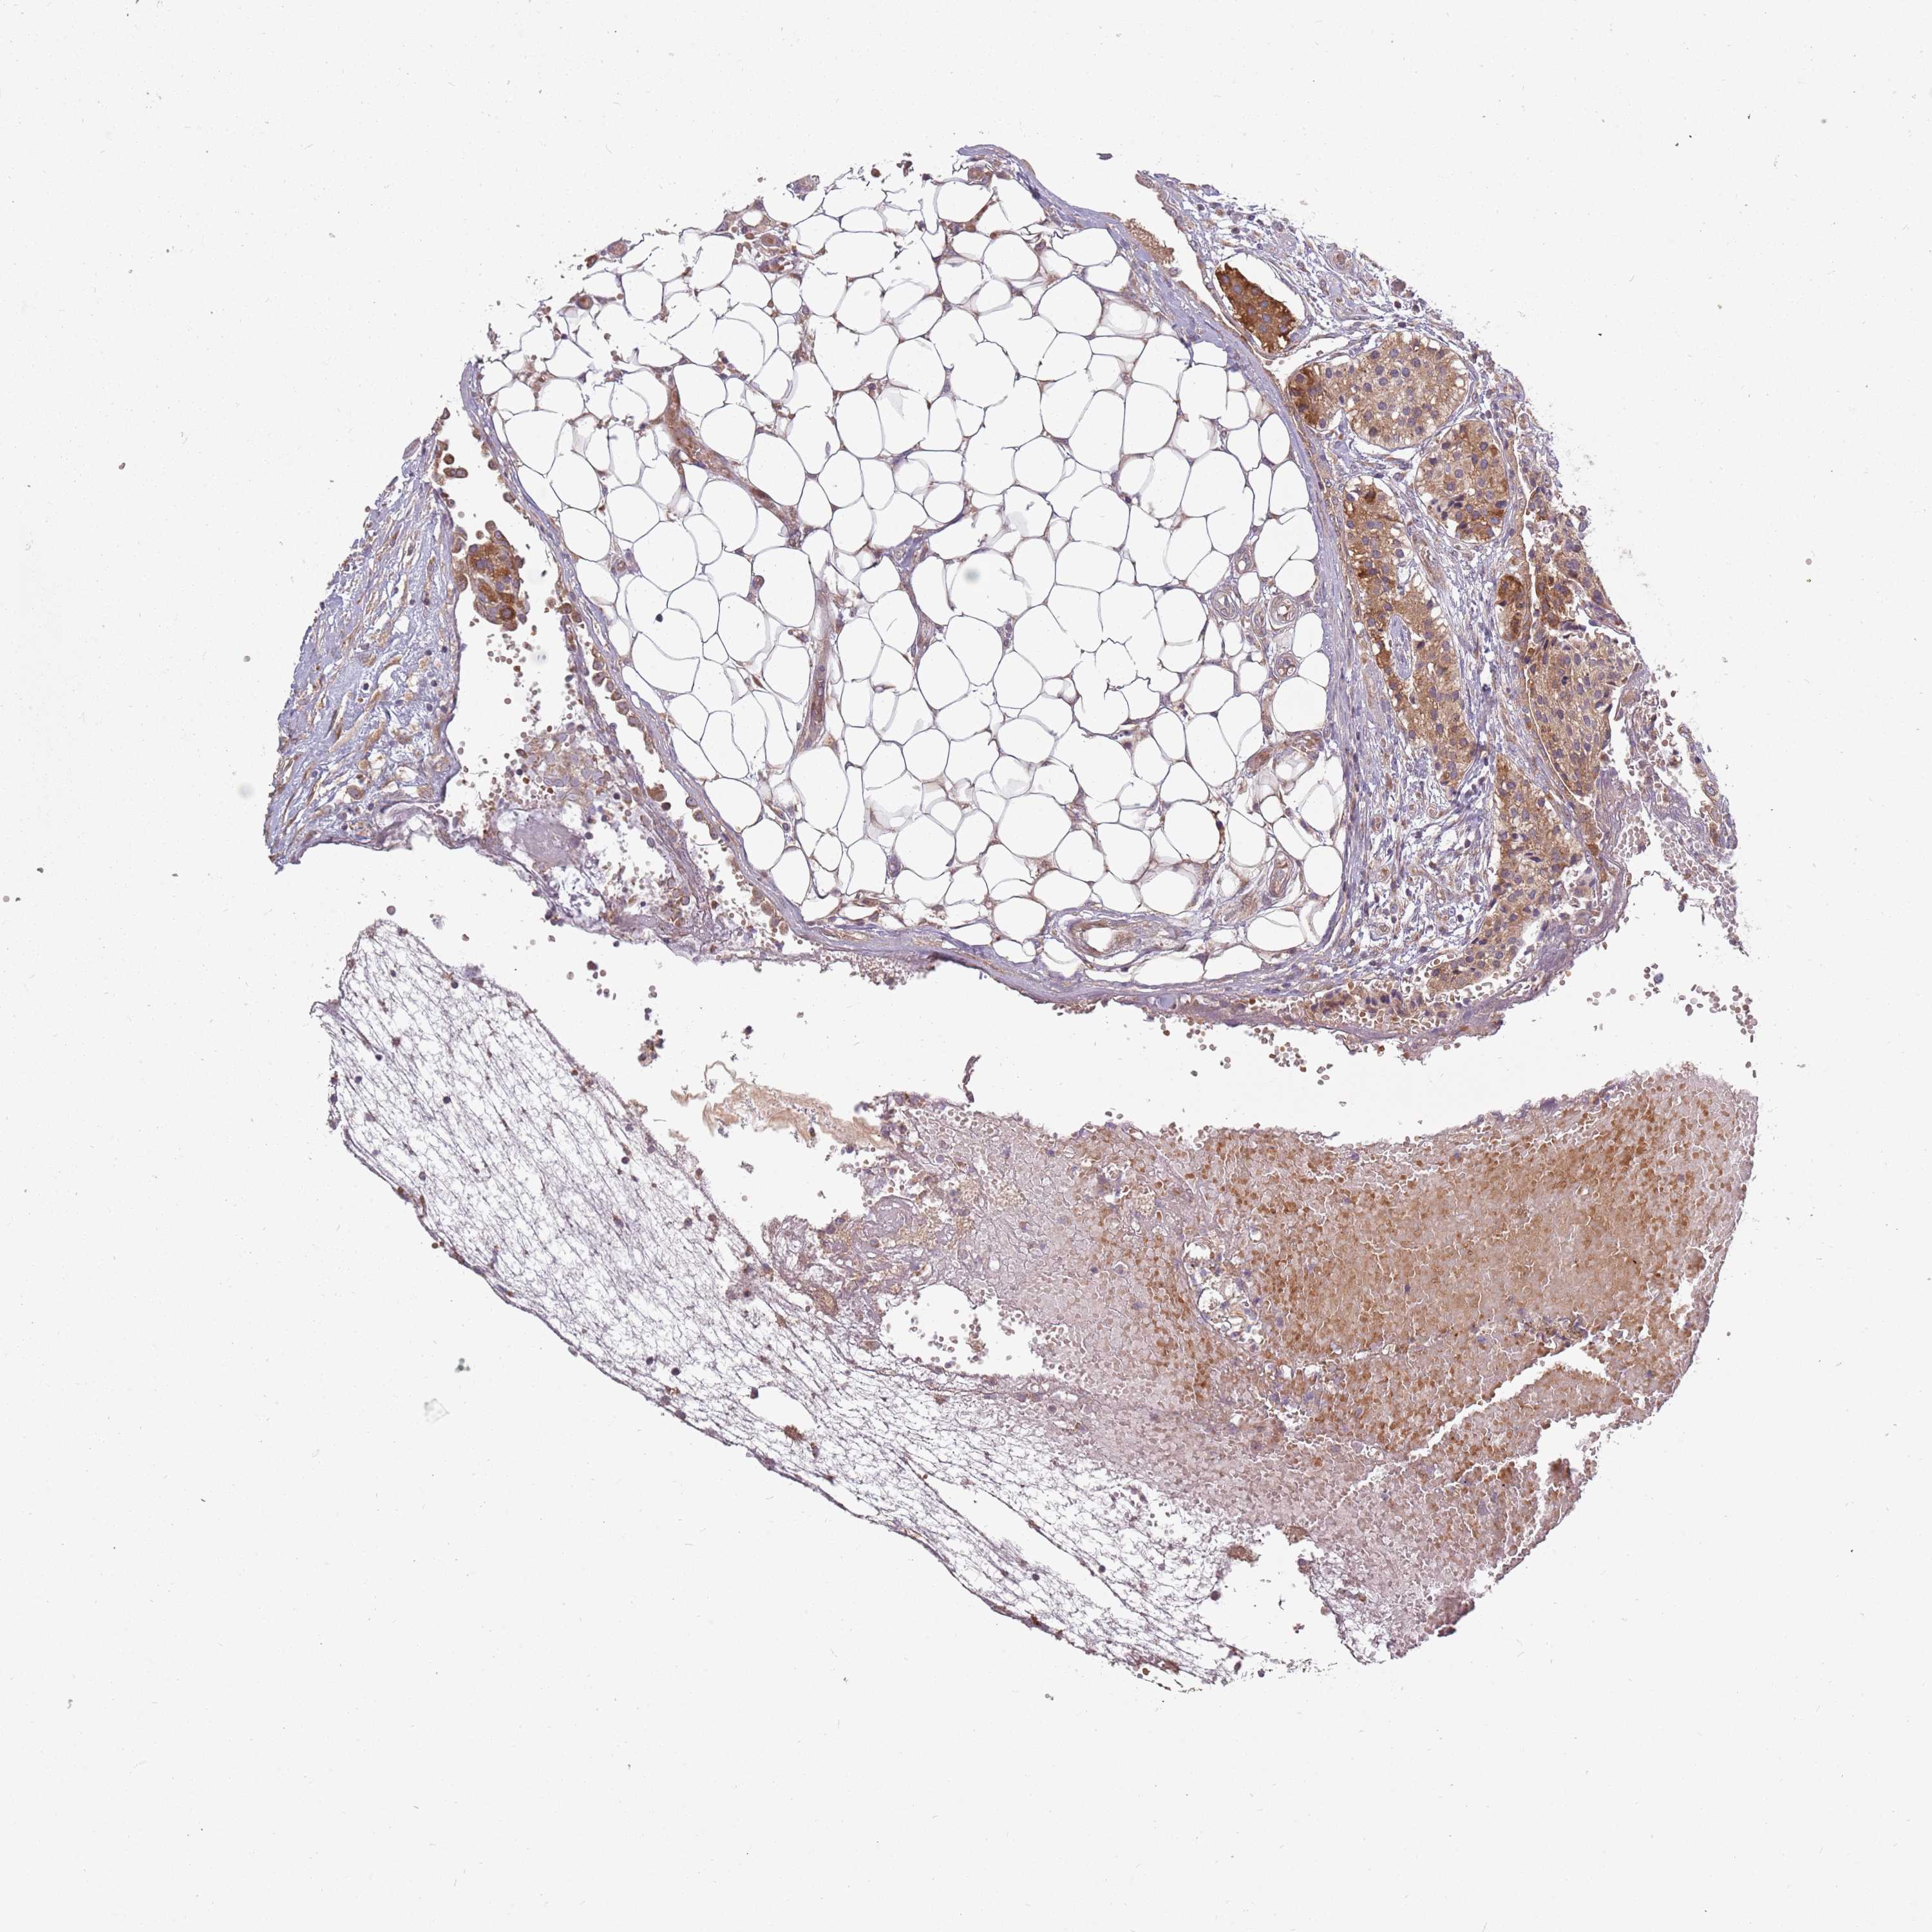

CARCINOID - Protein expressioni

A mouse-over function shows sample information and annotation data. Click on an image to view it in a full screen mode. Samples can be filtered based on level of antibody staining by selecting one or several of the following categories: high, medium, low and not detected. The assay and annotation is described here.

Each image is clickable and will lead to virtual microscopy that enables deeper exploration of all samples and also displays staining intensity scores, fraction scores and subcellular localization as well as patient and tissue information for each sample.

Antibody HPA049345

Staining

High

Intensity

Strong

Quantity

>75%

Location

Nuclear

Carcinoid, malignant, NOS

Carcinoma, NOS